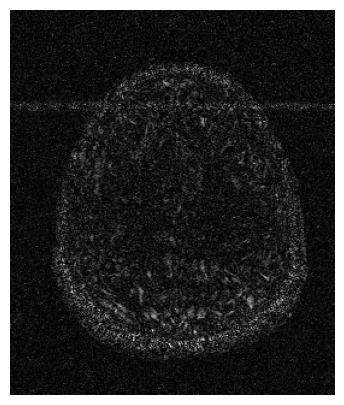

We used the PSNR and SSIM metrics to quantitatively compare the reconstructed magnitude image and the ground truth. They are given for each contrast and for the 2 acceleration factors in the Figs. 2- 3. Similar results are available on the public fastMRI leaderboard333fastmri.org/leaderboards, although generally slightly better. It is a bit difficult to consider these results when compared to only the zero-filled metrics, but these quantitative metrics do not accurately capture the performance of the GRAPPA algorithm [2]. However, at the time of submission, this approach ranks 2nd in the fastMRI leaderboards for the PSNR metric, and finished 2nd in the 4 and 8 tracks of the fastMRI 2020 brain reconstruction challenge [16].

Qualitative.

The visual inspection of the images reconstructed (available in Fig. 2) at acceleration factor 4 shows little to no visible difference with the ground truth original image. However, when increasing the acceleration factor to 8, we can see that smoothing starts to appear which leads to a loss of structure as can be seen in Fig. 3.